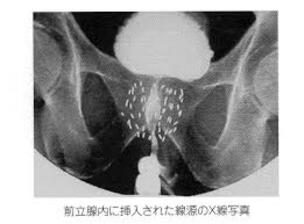

この画像は、前立腺がんの治療において放射線源を体内に埋め込む「小線源治療」のレントゲン写真です。

画像内の白く写っている小さな粒子は、ヨウ素125と呼ばれる放射性物質が入ったシード線源です。

これらの線源は、がん細胞を体の内側から直接照射して根治を目指すために、前立腺内に永久的に留置されます。

線源は通常、約1年間にわたり放射線を放出し続けます。